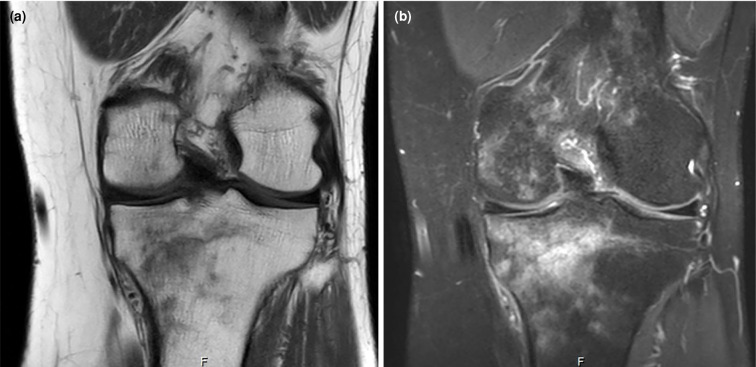

Intraosseous lipomas (IOLs) are rare benign bone tumors which can closely mimic malignancy on imaging, leading to diagnostic challenges. A 34-year-old male patient was admitted with persistent knee pain which was initially suspected to be metastatic bone disease. The patient reported activity-related pain relieved by rest. Physical examination revealed mild tenderness without swelling or restricted motion. Laboratory findings, including serum calcium and inflammatory markers, were normal. Magnetic resonance imaging (MRI) showed hyperintense lesions in the tibial and femoral metaphyses with surrounding bone marrow edema, raising suspicion of malignancy. Bone scintigraphy revealed increased radionuclide uptake in the tibial tuberosity, iliac crest, and the ninth rib, further mimicking metastatic disease. A biopsy of the tibial lesion confirmed mature adipocytes without necrosis or atypia, diagnosing IOLs. The patient was managed conservatively with non-steroidal anti-inflammatory drugs and physiotherapy. At three months, symptoms resolved completely, with no recurrence or new complaints. Follow-up MRI confirmed lesion stability. In conclusion, this case highlights the diagnostic complexity of IOLs and emphasizes the need for multimodal imaging and histopathological confirmation to differentiate benign lesions from malignancies. Including IOLs in the differential diagnosis of unexplained bone pain can prevent unnecessary invasive procedures and mistreatment.